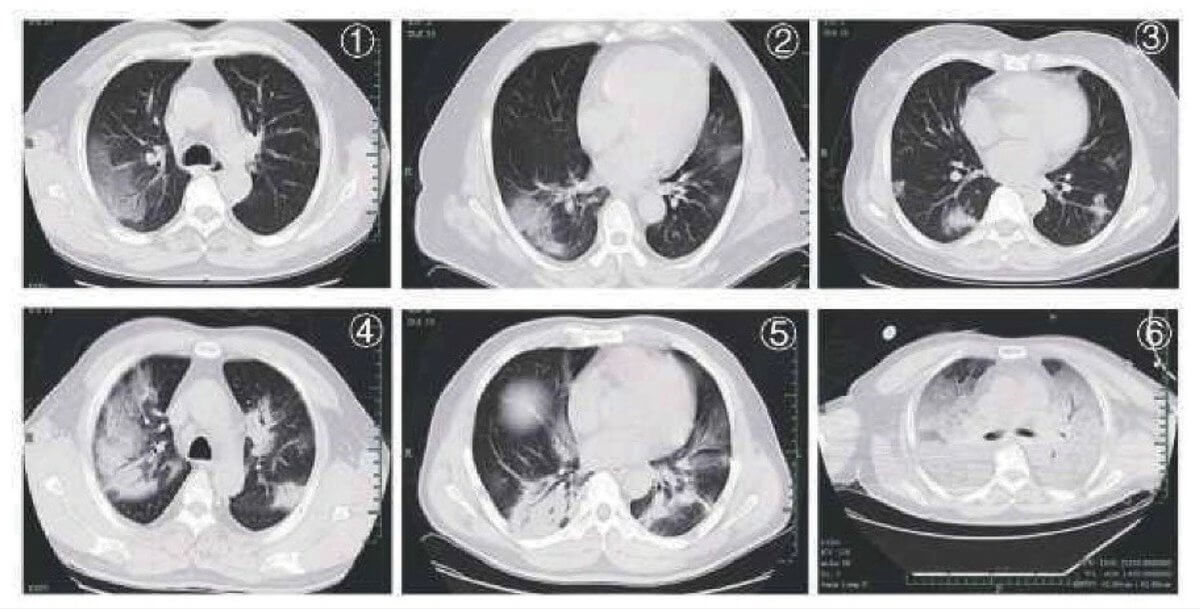

Признаки COVID19 на снимках компьютерной томографии

Компьютерная томография позволяет обнаружить специфические изменения, даже при отсутствии симптомов ковид. На КТ-изображениях вирус может проявляется в виде двустороннего затемнения («матовая стенка») и легочных уплотнений. Также на ранней стадии выявления вируса появляются узловатые затемнения, периферическая локализация, симптом «булыжной мостовой». Одним из признаков проявления коронавирусной инфекцией может служить и одиночное узловое затемнение на легочной ткани. У некоторых пациентов именно этот признак был выявлен на ранней стадии заболевания, когда еще не появились клинические признаки. Также важно отметить, что на снимках отсутствует лимфаденопатия (увеличение лимфатических узлов), легочные деструкции и плевральный выпот (избыток жидкости в соединительной ткани).